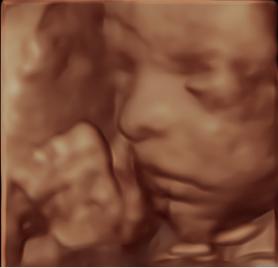

What is 3D/4D Imaging?

1

3D and 4D ultrasound are advanced imaging techniques that allow you to see detailed, three-dimensional images of your baby. 3D imaging produces a still, lifelike image, while 4D adds the element of real-time movement — so you may see your baby yawning, stretching, or even smiling.

Our Expertise

2

At Central West Women’s Imaging, 3D/4D imaging is available for all women as part of our routine obstetric assessment. This is part of our commitment to providing the highest standard of obstetric ultrasound in regional New South Wales. Our sonographers are experienced experts in 3D/4D imaging techniques and use dedicated GE women’s imaging equipment optimised for this purpose.

While we are committed to giving you the best possible experience, we are unable to guarantee a particular 3D/4D image, as this depends on your baby’s position and the amount of fluid around them on the day. Our first priority is always a thorough, high-quality diagnostic ultrasound — we will do all we can within your appointment time to also capture 3D/4D images for you.